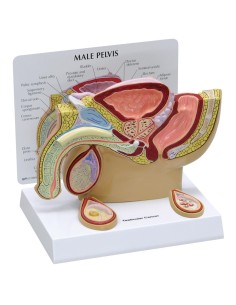

Pelvis masculin 3B Scientifique avec ligaments, vaisseaux, nerfs, plancher pelvien et...